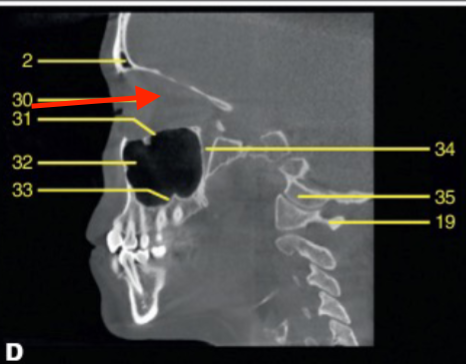

mental foramen

what is the structure indicated by the arrow

hard palate

identify the structure

mandibular condyle

C2 odontoid process

what is 43

coronoid process

what is 52

orbit

what is 6